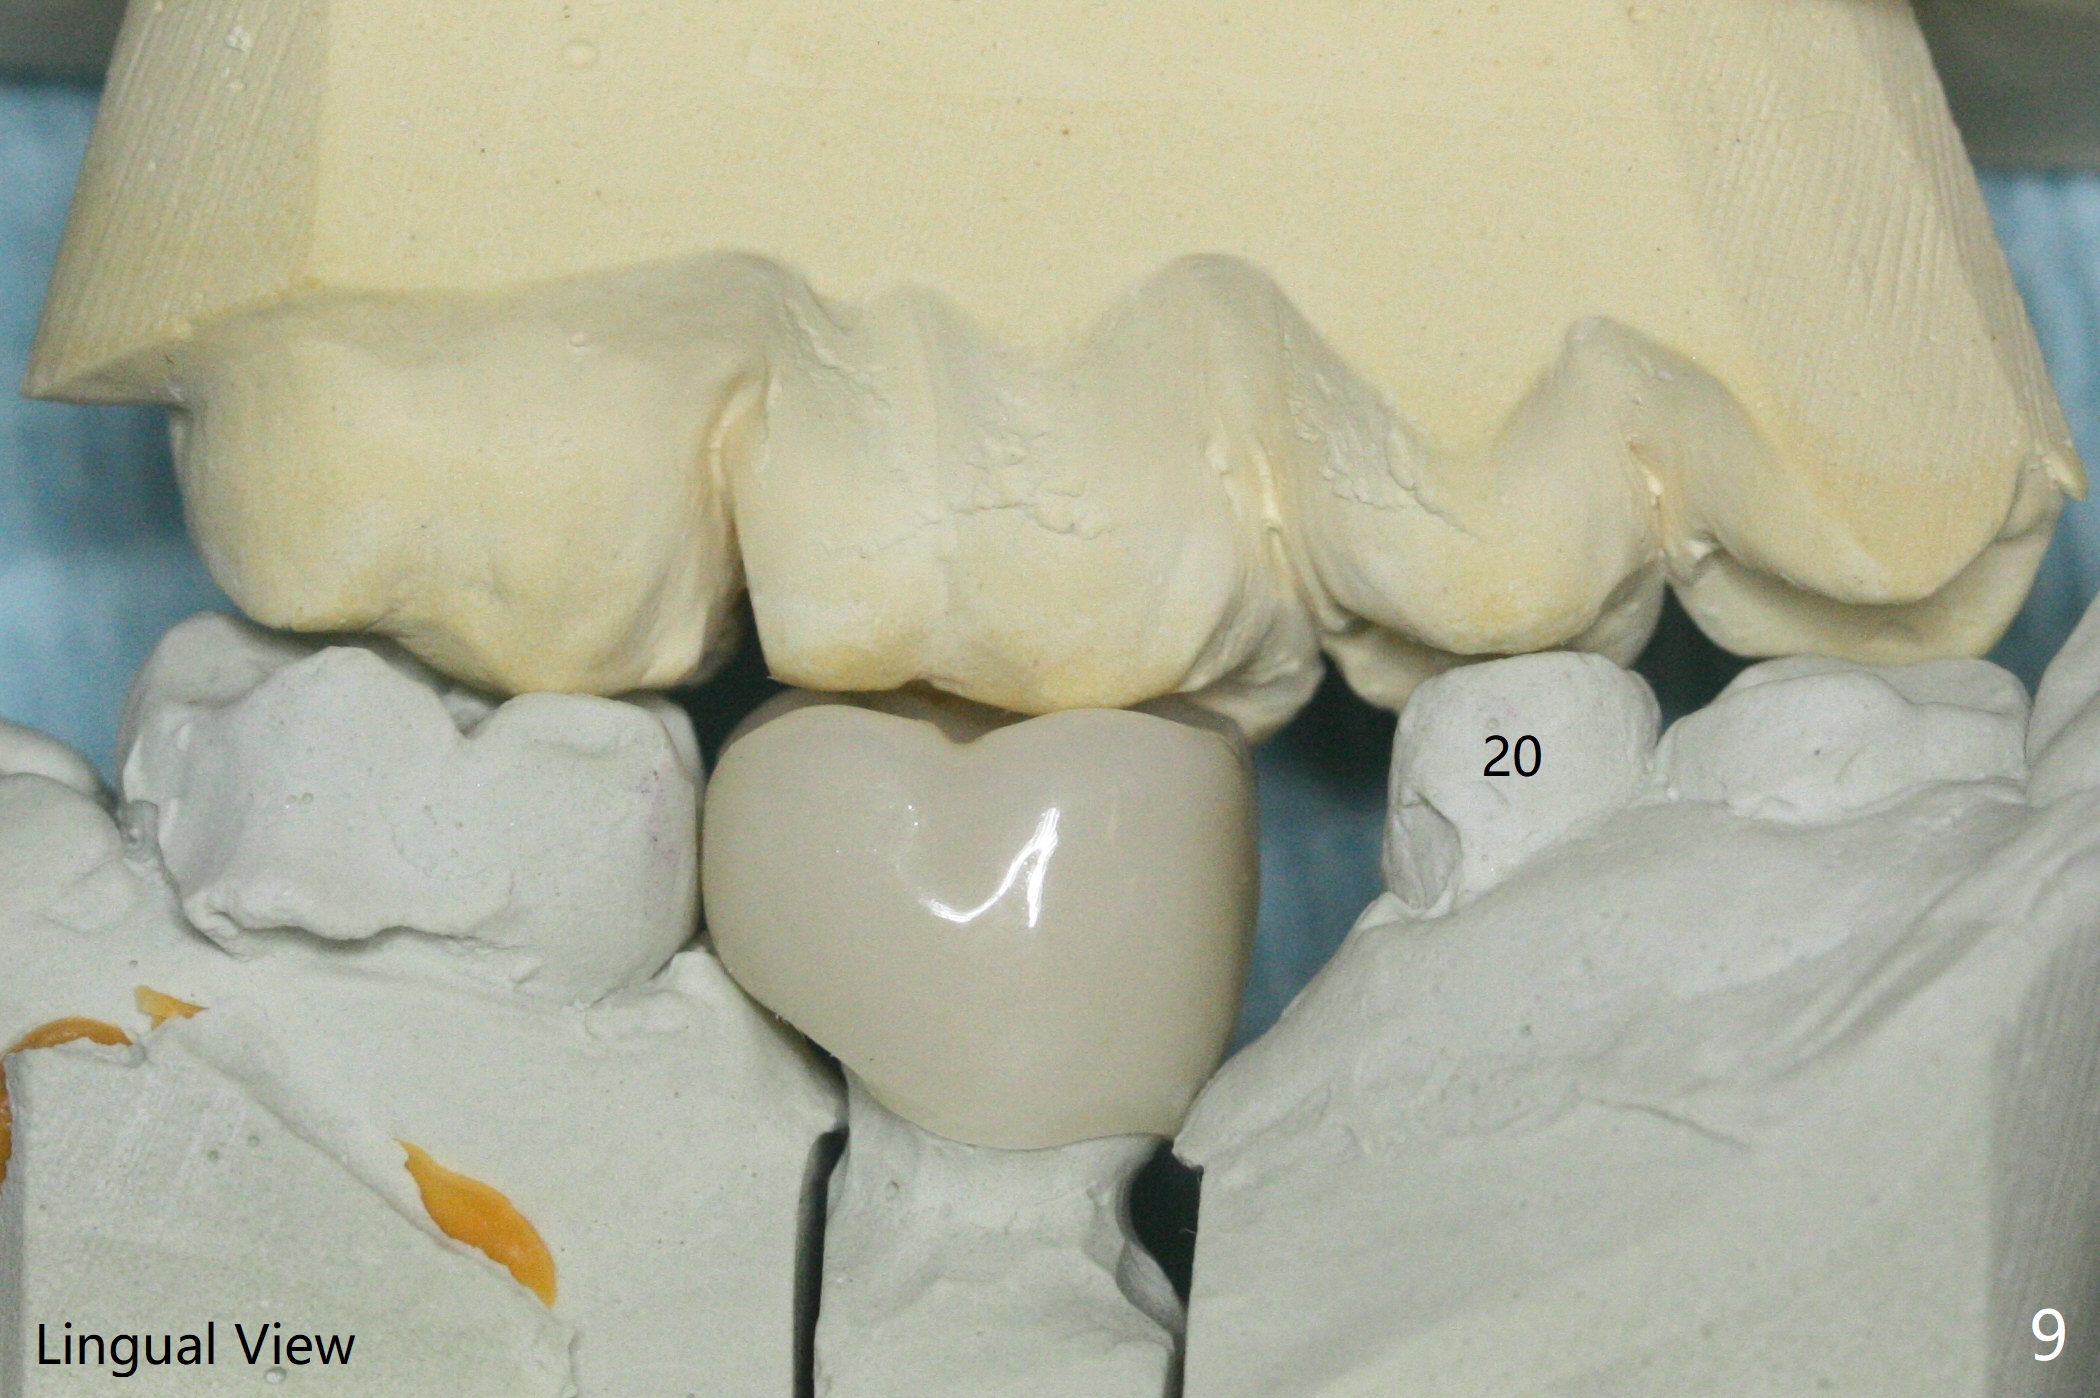

With 34 mg of Lidocaine and 17 mcg of Epinephrine (local infiltration), a 4.5x8.5 mm implant is placed with guide. The insertion torque is ~50 Ncm. It is placed in precise depth and in a short period of time (tolerable to the operators and patient, easier than mini-implant placement, Fig.1). There is no postop pain or paresthesia. The mesidistal position is within treatment plan (Fig.2). Miniimplants are placed to intrude #14 14 days prior. The teeth #16,17 and 32 are extracted 3 months postop. Minimal bone resorption at the crest is noted nearly 4 months postop (Fig.3). Bands and brackets are placed #18 upright 4 months postop (Fig.4 (14 niti wire)). The buccal and lingual view of the preop model shows that the supraerupted 1st molar (#14) has close relationship with the distal surface of the tooth #20 (Fig.5,6), accounting for the severe wear of the latter (Fig.8-11). The implant not only acts as an anchor to upright #18 in 4.5 months post banding (Fig.7 *), but also as an occlusal stop so that #18 has no interference to be moved. The stress on the implant results in radiating trabecular pattern (Fig.7,11 (9,11 months postop), as compared to before loading (Fig.1,3)). Restoring the distal contour of #20 with composite (Fig.12 C) makes it easy to close the space by adding porcelain the mesial surface of the implant crown. The crown/abutment is loose in China 7 months post cementation.